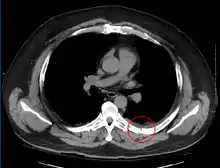

معرض صور